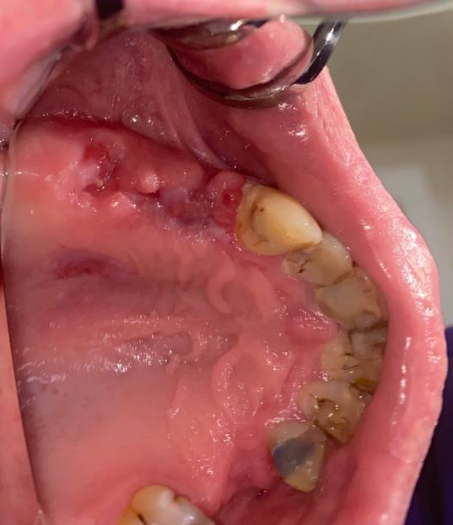

It'sGeorgy Опубликовано 28 мая, 2021 Поделиться Опубликовано 28 мая, 2021 Здравствуйте. 21.05.21: Язычносмещенный разрез, удаление оставленного корня 2.4, удаление 2.6 и 3.8. Имплантаты 2.4, 2.5. Пошел сделал снимок: Не понравился дистальный наклон 2.5, пошел перекручивать. Пока крутил-вертел торк с 25 упал до пальцевого. Принял решение установки коротких формиков, ССТ вестибулярно и ушивания наглухо. Сегодня пациент пришел на осмотр к другому доктору, а там вот такая печалька: Какие ошибки предполагаю сам: 1. Слишком толстый трансп, ушивание которого вызвало перенатяжение 2. Медиальный шов, который держит трансп совсем хиленький и, на самом деле, мало что держит. И главный вопрос: что делать? Оставлять и надеяться, что что-то приживется или полностью убирать? Ссылка на комментарий

stommm Опубликовано 28 мая, 2021 Поделиться Опубликовано 28 мая, 2021 Не трогайте. Что отвалится, то отвалится само со временем 1 1 Ссылка на комментарий

АнтонТЛТ Опубликовано 28 мая, 2021 Поделиться Опубликовано 28 мая, 2021 Пусть пока побудет, нижние слои хоть немного да прилипли. Рот не санирован, гигиена перед операцией не сделана. Какой смысл в свободном трансплантате был? Ссылка на комментарий

Карен Аванесов Опубликовано 29 мая, 2021 Поделиться Опубликовано 29 мая, 2021 Ждать, полоскать пассивно или лизобакт, а на будущее, при таком шикарной ретромолярной области, не трогать болезненное небо. 11 часов назад, АнтонТЛТ сказал: Пусть пока побудет, нижние слои хоть немного да прилипли. Рот не санирован, гигиена перед операцией не сделана. Какой смысл в свободном трансплантате был? Доктор получил опыт и выводы сделает. 1 Ссылка на комментарий

Irouil Опубликовано 29 мая, 2021 Поделиться Опубликовано 29 мая, 2021 (изменено) Я бы все, что совсем некротическое, аккуратно срезал Изменено 29 мая, 2021 пользователем Irouil Ссылка на комментарий

АнтонТЛТ Опубликовано 12 июня, 2021 Поделиться Опубликовано 12 июня, 2021 (изменено) Какие ошибки вижу. 1)Разрез смещен небно, сосуды кровоснабжающие десну идут вестибулярно и небно, на вершине альвеолярного отростка самые конечные "ветви", т.е. самые тонкие. Из-за небного разреза край вестибулярного лоскута потерял часть питания. 2) Лоскут ушит с натяжением, т.к. не было мобилизации, и где были швы лоскут пережат. Опять же нарушение питания. 3) Трансплантат пришит большими П-образным швами, которые пережимают сосуды вестибулярного лоскута. 4) Трансплантат лежит поверх имплантатов, значит ушивание раны было не стык в стык. И рассчитывать на заживление первичным натяжением не особо нужно. 5) Про толщину трансплантата уже было сказано, могу добавить что трансплантат должен питаться от покрывающего лоскута и от кости. Площадь контакта с костью снижена из-за наличия имплантатов. Изменено 12 июня, 2021 пользователем АнтонТЛТ 3 Ссылка на комментарий

Irouil Опубликовано 12 июня, 2021 Поделиться Опубликовано 12 июня, 2021 Практически слово в слово согласен с Антоном Потребители кровоснабжения - трансплант и края раны. Доноры - кость и основания лоскутов. В Вашем случае графт отнимает у вестибулярного края раны и от основания, и от кости. Сам он, при этом, недополучает от кости из-за железок, на которых лежит, следовательно просит у лоскута еще больше. Зато небный край раны получает избыток питания, который там нафиг не нужен. 1 Ссылка на комментарий